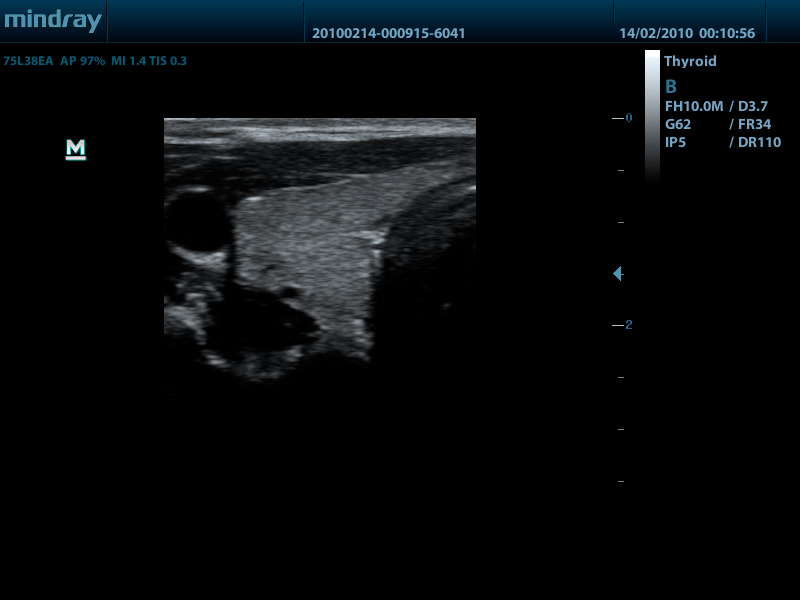

Линейный датчик 75L38EA (5.0/7.5/8.5/10.0/Н8.0/Н10.0 МГц, 38 мм)

Линейный датчик 75L53EA (5.0/7.5/8.5/10.0/Н8.0/Н10.0 МГц, 50 мм)